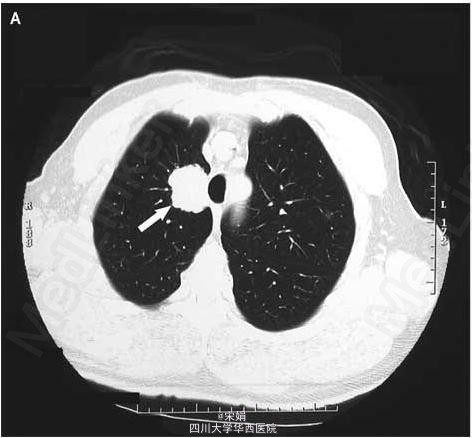

患者为63岁老年男性,胸片发现右肺肿块来诊。

胸部CT示右肺上叶靠近纵膈处有一软组织密度肿块,与气管旁软组织紧密连接。支气管镜下见气管管腔形态正常。